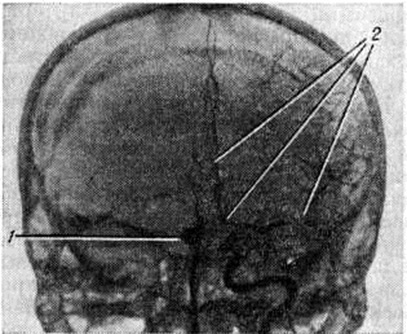

Эпидуральные и субдуральные кровоизлияния в подавляющем большинстве случаев наблюдаются при черепно-мозговой травме (смотри полный свод знаний). Субарахноидальное кровоизлияние возникает наиболее часто вследствие разрыва врождённых мешотчатых или артериовенозных аневризм (смотри полный свод знаний: Аневризма сосудов головного мозга), располагающихся чаще всего в местах разветвления сосудов основания головного мозга (рисунок 1). Некоторые инфекционные болезни, например, грипп (смотри полный свод знаний), геморрагические лихорадки (смотри полный свод знаний) и другие, при тяжёлом течении иногда могут сопровождаться Подоболочечные кровоизлияния Нередко Подоболочечные кровоизлияния возникают в пожилом возрасте у больных атеросклерозом при разрыве склерозированных сосудов мозговых оболочек, а также при хронический воспалительных процессах в твёрдой оболочке мозга, сопровождающихся поражением вен (смотри полный свод знаний: Пахименингит). Развитию Подоболочечные кровоизлияния способствуют заболевания печени, крови, авитаминозы, приводящие к развитию геморрагического синдрома. В ряде случаев Подоболочечные кровоизлияния могут сопутствовать кровоизлияниям в вещество головного мозга при гипертонической болезни, располагаясь часто в задней черепной ямке на поверхности полушарий мозжечка или ствола мозга (рисунок 2, 3). Скопление крови в задней черепной ямке нарушает отток цереброспинальной жидкости и создаёт условия для развития окклюзионной гидроцефалии (смотри полный свод знаний) и отёка мозга (смотри полный свод знаний: Отёк и набухание головного мозга). Вызвать Подоболочечные кровоизлияния могут резкие наклоны туловища, физическая нагрузка, эмоциональное напряжение, сопровождающиеся значительным подъёмом АД.